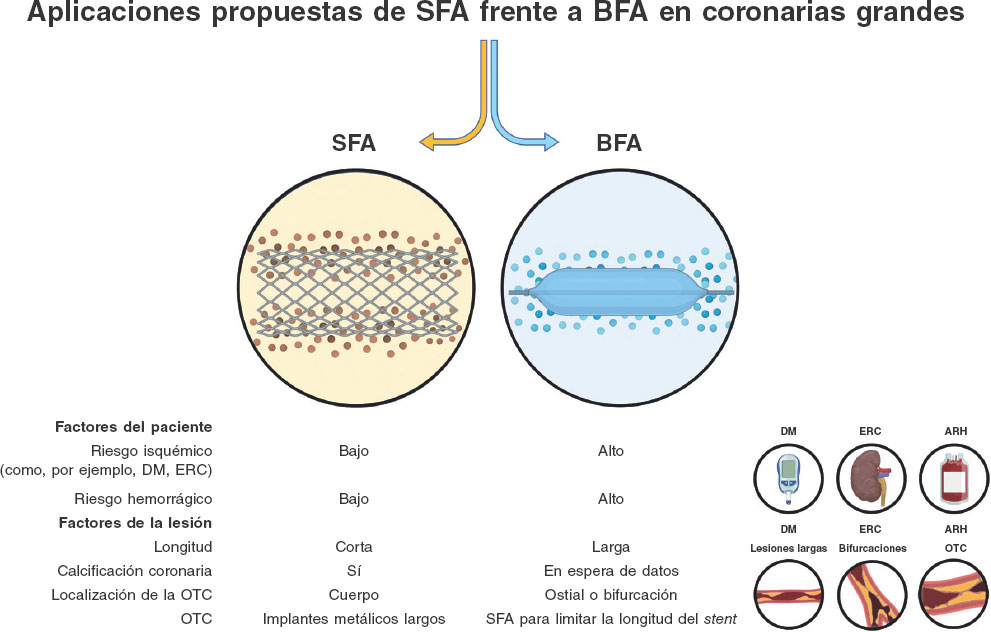

Balones farmacoactivos: a la conquista de la enfermedad coronaria de vaso grande

Artículos originales

Editoriales